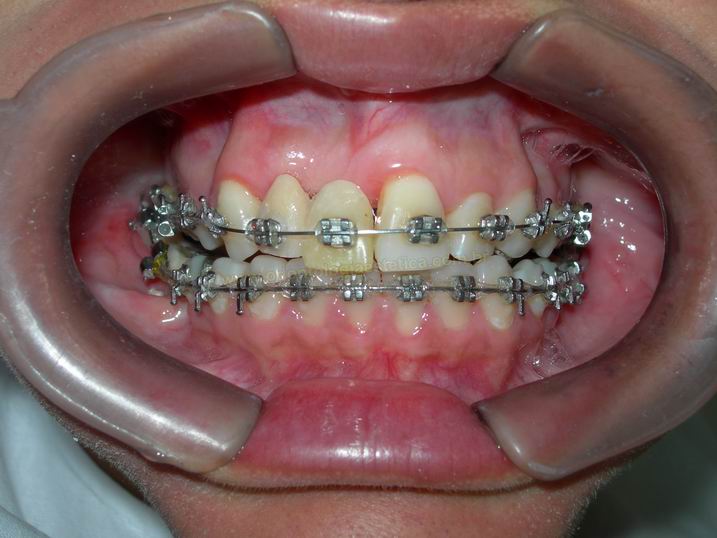

FASE AVANÇADA DO TRATAMENTO ORTODÕNTICO APÓS ABERTURA DE ESPAÇO PARA A INSTALAÇÃO DE DOIS IMPLANTES

FASE AVANÇADA DO TRATAMENTO ORTODÕNTICO APÓS ABERTURA DE ESPAÇO PARA A INSTALAÇÃO DE DOIS IMPLANTES |